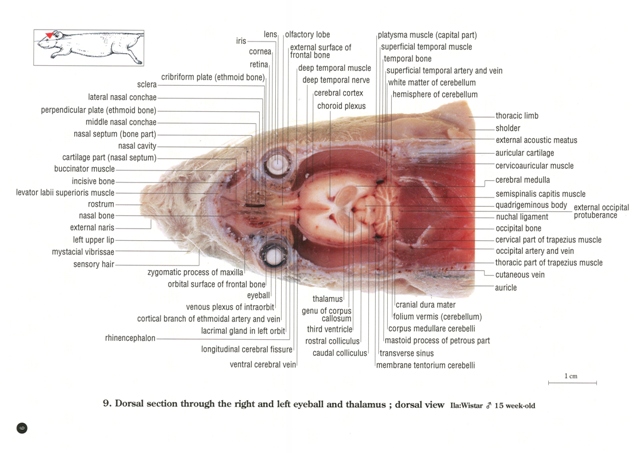

お得な情報満載 ラットの断面解剖アトラス 出版事業 - 医学一般